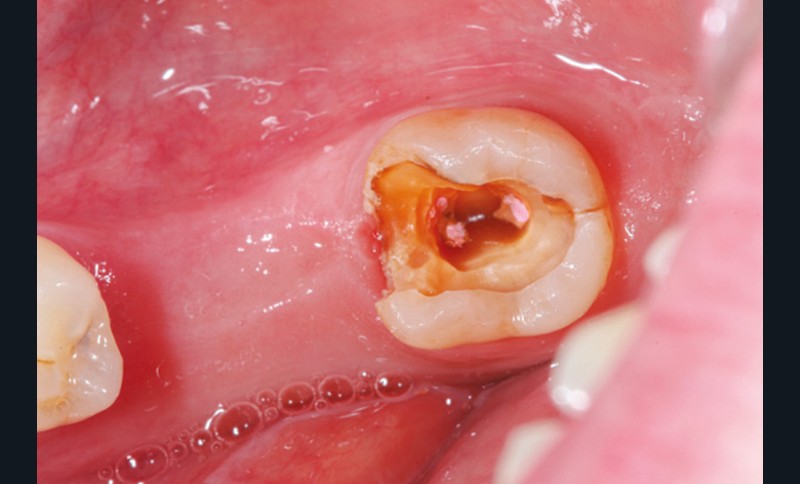

La répartition de la charge occlusale sur l’ensemble d’une arcade est aussi perturbée après une ou plusieurs extractions, ce qui peut occasionner des surcharges occlusales pour les dents restantes. Selon le délabrement coronaire de la dent [10], une fracture coronaire amélo-dentinaire ou corono-radiculaire peut intervenir sous cette surcharge occlusale et engager le pronostic de la dent concernée (fig. 14 à 17).